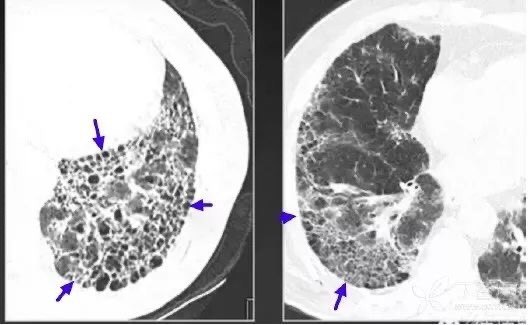

反晕征

顾名思义,表现与晕征相反,是一种外带密度略高(白箭)于内部磨玻璃密度区(蓝箭)的 CT 表现。一般常见于肺结核和真菌肺炎。